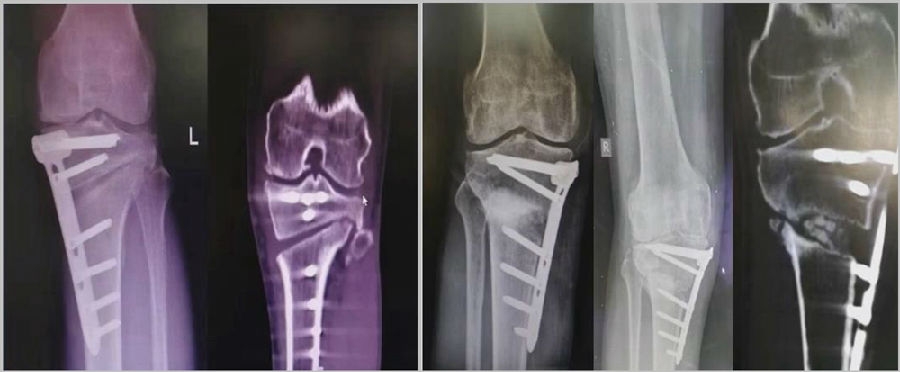

2、处理

(1)如果在手术台上,或是刚做完手术就发现矫正不良问题,此时比较简单。需要先跟患者进行沟通,在手术中直接将远端4颗螺钉卸下来,调整好力线后重新打入即可。但是注意要把远端单皮质螺钉换成双皮质螺钉。

(2)如果患者已经达到初始愈合,此时如果出现过度外翻,需要在内侧重新做内侧闭合楔。

(3)如果做完手术时间较长,出现过度矫正或矫正不足时,需要重新做力线分析,看一看力线在哪个方向可以再进行调整。胫骨侧有调整余地,就在胫骨侧进行调整;股骨侧需要调整,就在股骨侧进行调整。